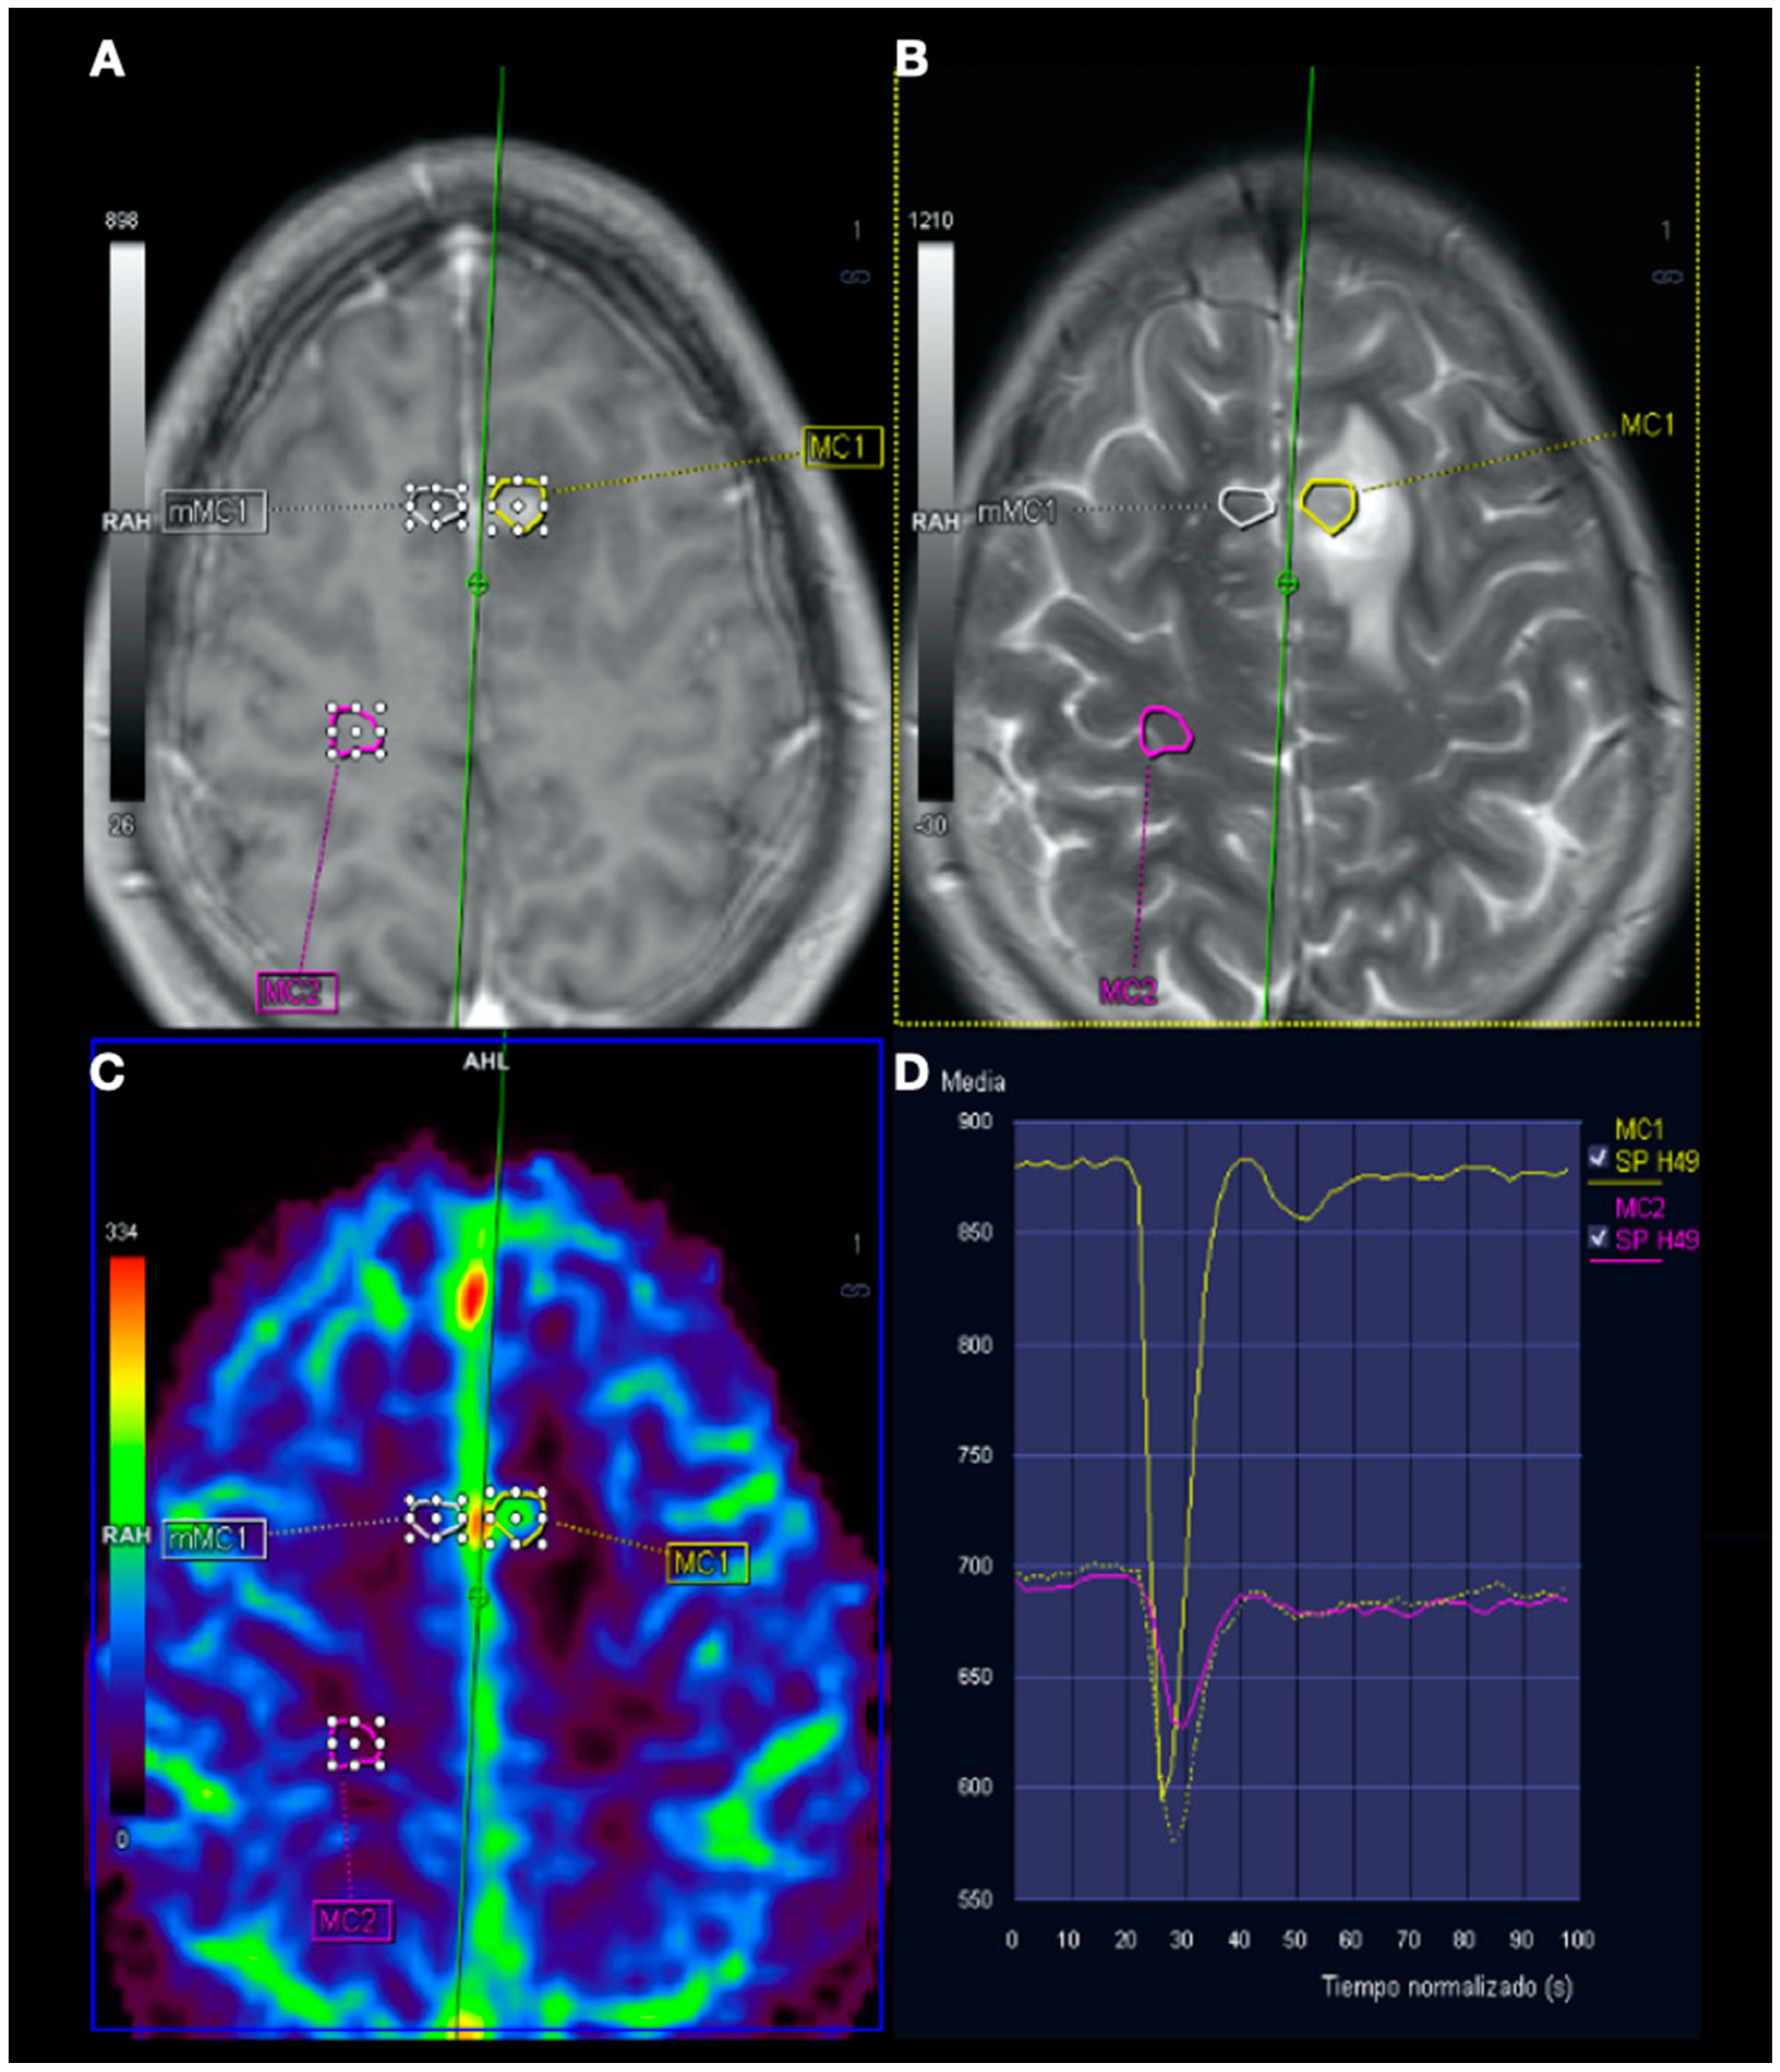

Figure 5.

Magnetic resonance imaging (MRI) perfusion: Image (A), Gd T1WI; image (B), T2WI; image (C), MRI perfusion map corresponding to the corrected cerebral blood volume (CCBV); image (D), average curve. In the contrast enhancement area, there is an increase in cerebral blood volume (CBV) in relation to the contralateral side and normal subcortical white matter. In the average curves, the area under the curve is higher in the enhancement zone than in the other two zones.

In this complex scenario, we report an uncommon case of DCS in a spearfishing breath-hold diver. The diver had a high-risk dive profile, with repetitive breath-hold dives to a maximum depth of about 30 m for several hours and short surface intervals. He had a good response to hyperbaric chamber treatment (US Navy Table 6) and was clinically asymptomatic. Neuroimaging findings showed hyperintensity in long-TR sequences (FLAIR, T2WI), as well as in ADC mapping, and no hyperintensity in DWI sequences, compatible with the presence of vasogenic edema in the left frontal and right temporal lobes (Figure 3 and Figure 4). Regarding MRI perfusion, in the contrast enhancement area, there was an increase in cerebral blood volume (CBV) in relation to the contralateral side and normal subcortical white matter. In the average curves, the area under the curve was higher in the enhancement zone than in the other two zones, which would indicate an increase in perfusion (Figure 5). Initially, given the atypical nature of the lesions, with irregular enhancement in T1WI with intravenous contrast (although their radiological characteristics were not suggestive of neoplastic etiology) [22,23], an extension study with body CT was completed, showing no presence of neoplasia. Likewise, prior to the neuroimaging study, a vascular study (neurosonological, echocardiographic) was performed, as was an extensive blood test study, with no pathological findings. The radiological evolution of the lesions tended towards resolution, with minimal chronic lesions persisting, compatible with small areas of cerebral malacia (Figure 6).

These approaches involving endothelial and BBB dysfunction are of recent interest, having been proposed as a key element in the pathophysiology of other clinico-radiological entities such as PRES [35]. Traditionally, the theory proposed for the pathophysiology of PRES was that rapid increases in blood pressures may exceed and overcome the autoregulatory capabilities of the cerebral vasculature, causing vascular leakage and resultant vasogenic edema [35,36]. However, we now know that up to 30% of patients with PRES do not have the high blood pressures necessary to exceed the autoregulatory control of the cerebral vasculature. Here, endothelial dysfunction would be the main culprit, which in turn could be caused by various toxins, immunosuppressive drugs, chemotherapy or septic conditions, among others [35,36,37,38,39]. In PRES, T2WI and T2 FLAIR sequences are probably the most useful, given their sensitivity for detecting vasogenic edema on MRI, as well as DWI sequences and the ADC map. Although the lesions most frequently described in PRES have a bihemispheric distribution and usually involve the parieto-occipital lobes, other locations have been described, with areas such as the frontal and temporal lobes being more common (up to 68% and 40%, respectively) [35,36]. Regarding the radiological evolution of the lesions, PRES-related findings are usually reversible, with normalization of clinical and imaging findings once the underlying etiological cause is resolved. However, in some cases, areas of restricted diffusion may eventually lead to permanent lesions in the brain parenchyma [35]. In this case, ADC map images could have prognostic relevance, since higher values have been associated with lesion reversibility; in contrast, attenuated ADC values would indicate cerebral ischemia and poor neurological outcome [36,37]. The increase in corrected CBV in MRI perfusion would also support the PRES hypothesis with respect to the ischemic mechanism (stroke-like), where it would be decreased. On this last point, there is a potential influence of the increase in cerebral blood flow associated with hypoxemia, with different studies currently showing an increase in blood flow in the middle cerebral artery possibly due to the increase in arterial PaCO2 or hypoxia, among others [40,41,42,43].